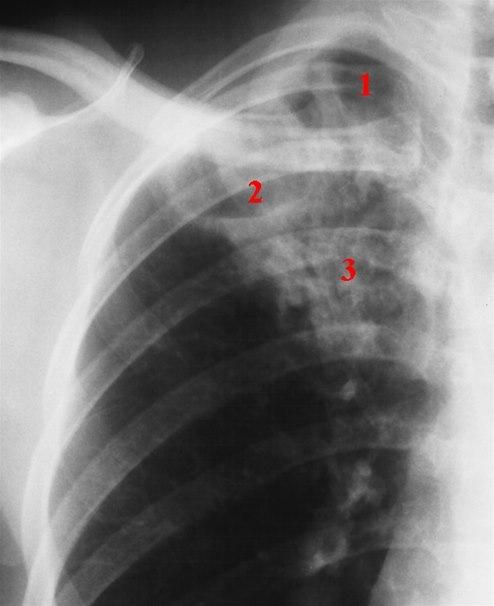

Lungerøntgen

Lungetuberkulose er den viktigste tuberkuloseformen, og den eneste varianten av tuberkulose som er smittsom. Når det påvises en positiv blodtest (IGRA), tas det derfor alltid lungerøntgen etterpå for å bekrefte eller avkrefte om det foreligger aktiv lungetuberkulose.

Hvis lungerøntgen viser tegn til aktiv tuberkulose, må det gjøres direkte mikroskopi og tas dyrkningsprøver av oppspytt eller skyllevæske fra bronkiene. Pasienter med positiv mikroskopi er mer smittefarlige enn de med negativ mikroskopi. Resultat av direkte mikroskopi av oppspytt (ekspektorat) er avgjørende for å kunne vurdere smittsomhet. Dersom tuberkelbakteriene lar seg påvise ved mikroskopi, vil diagnosen være klar i løpet av få timer.